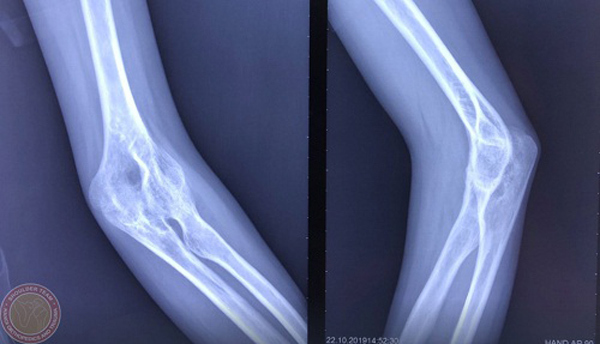

BS Nguyễn Hữu Mạnh, Trưởng Đơn nguyên Phẫu thuật Vai và Khuỷu, BV đa khoa Xanh Pôn cho biết, khi đến khám, tình trạng viêm khớp dạng thấp của chị Ngân khá nặng, khuỷu tay và 2 bàn tay bệnh nhân đã bị biến dạng hoàn toàn, trong đó nặng nhất là khớp khuỷu trái bị dính hoàn toàn không còn chức năng vận động.

Với trường hợp này, phương án tối ưu nhất là thay khớp khuỷu. Tuy nhiên, việc phẫu thuật cũng sẽ rất khó khăn do các xương đã dính liền lại với nhau.

Sau hội chẩn kĩ càng, các bác sĩ vẫn quyết định thực hiện thay khớp khuỷu cho chị Ngân. Đây cũng là bệnh nhân viêm khớp dạng thấp đầu tiên tại Việt Nam được phẫu thuật thay toàn bộ khớp khuỷu để phục hồi lại chức năng cho cánh tay bị tàn phế.